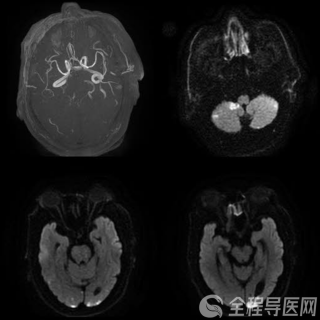

经过一夜补钠治疗,次日清晨赵大姐精神微微好转,但仍处于昏睡到浅昏迷状态之间。刘海艳查房时发现,赵大姐看上去比实际年龄偏老,体毛非常稀疏,乳房干瘪,女性特征不是很明显,而且声音有些粗哑。她继续询问赵大姐病史,一位亲戚告诉她赵大姐30多岁已经停经,而且再生了二女儿之后曾出现过产后大出血。鉴于赵大姐的体征和既往病史,刘海艳脑海中浮现出席汉综合征这种疾病。随后的检查结果证实,赵大姐存在甲状腺功能低下、性腺功能低下、皮质醇功能低下等病症,因此可以确诊她的确患上了脑垂体障碍引起的罕见疾病——“席汉综合征”。